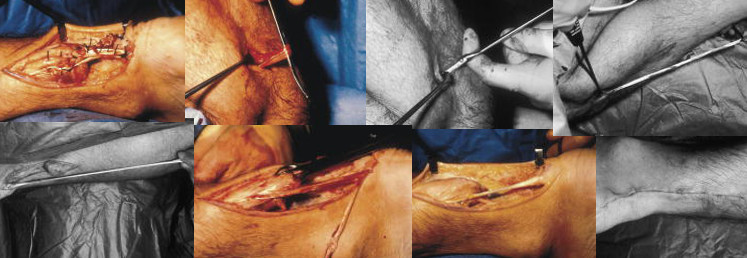

1.开创缝合:

2.经皮缝合法

3.V-Y 肌腱瓣修补术治疗陈旧性跟腱断裂

4.自体股薄肌移植

5.自体腓骨短肌移植

6.关节镜下跟腱缝合术